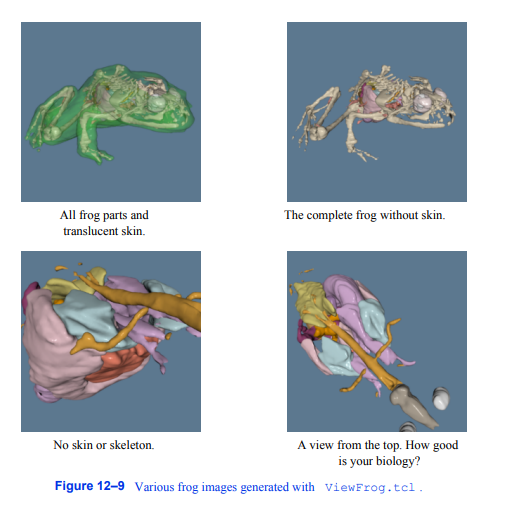

一旦模型按照上述流程生成,就可以使用下面的名为ViewFrog的tcl脚本进行渲染。tcl。首先,我们创建一个Tcl过程来自动从模型文件中创建角色。所有管道元素的命名都与部件的名称后面跟着管道元素的名称一致。这使得用户很容易在更复杂的用户界面中识别每个对象。

图12 - 9显示了用ViewFrog生成的青蛙的四个视图。tcl。这个冗长的示例展示了像VTK这样的综合可视化系统的强大功能。

图12-9使用ViewFrog.tcl生成的各种青蛙图像